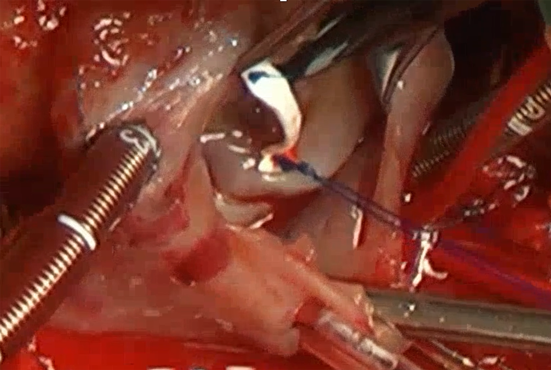

A male infant, born at 39 weeks of gestation and weighing 3,264 g, had been diagnosed with HLHS (mitral stenosis and aortic atresia) and hydrops fetalis due to severe tricuspid regurgitation and mild tricuspid stenosis detected on fetal echocardiography. This was confirmed by postnatal echocardiography. The Apgar score at birth was 7, and he was immediately intubated due to respiratory failure. Transthoracic echocardiography showed that the tricuspid valve diameter was 12 mm (90% of normal), with severe regurgitation and mild stenosis due to a dysplastic septal leaflet. At 4 days of life, bilateral pulmonary arterial banding was performed, and prostaglandin E1 infusion was administered to maintain the ductus arteriosus patent. Heart failure progressed due to restrictive patent foramen ovale and gradual closure of the patent ductus arteriosus; hence, the Norwood procedure and tricuspid valvuloplasty had to take place on 20 days of life. During the surgery, cardiopulmonary bypass was established via brachiocephalic trunk and bicaval cannulations. Bilateral pulmonary arterial bands were removed, the aortic arch was reconstructed, and atrial septal defect was enlarged. The tricuspid valve was tested using a saline solution injection; it showed moderate regurgitation at the center of the valve due to a dysplastic septal leaflet attached directly to the interventricular septum. Upon moving the anterior leaflet towards the septal leaflet, regurgitation appeared less. A bridge was then placed between the annula of the anterior and septal leaflets using an expanded polytetrafluoroethylene strip (1.5 mm wide, 0.4 mm thick) fixing with 5-0 polypropylene (Figs. 1 and 2, Video 1). We aimed at the strip length 80% of the normal mitral valve diameter. For fine adjustment, one end of the strip was sutured to the annulus of the anterior leaflet first. Then, we performed an injection test while pulling the other end to determine the optimal anteroposterior diameter, and eventually sutured the septal leaflet side. The saline solution injection test was repeated; since regurgitation became significantly less, no additional valvoplasty was performed. The final diameter of the tricuspid orifice was 10 mm (representing 87% of the normal range of the mitral valve). A 5-mm ring-reinforced expanded polytetrafluoroethylene graft was then interposed between the right ventricle and the pulmonary artery. Weaning from cardiopulmonary bypass was smooth, and the sternum was splinted with stable hemodynamics. Delayed sternal closure was performed on postoperative day 3. Due to refractory pleural effusion, hospital admission was prolonged and the patient was discharged on postoperative day 206. Echocardiography at discharge illustrated trivial tricuspid regurgitation and mild tricuspid stenosis (trans-tricuspid blood flow velocity 1.8 m/s). The bidirectional Glenn procedure was performed 11 months after the Norwood procedure, and the patient is awaiting total cavopulmonary bypass. Midterm echocardiography 19 months after the Norwood procedure revealed no tricuspid regurgitation and mild tricuspid stenosis (trans-tricuspid blood flow velocity 1.2 m/s).

Fig. 1 A bridge is placed between the annular hinges of the anterior and septal leaflets using an expanded polytetrafluoroethylene strip (1.5 mm wide, 0.4 mm thick)

Fig. 2 Intraoperative photograph of a bridging technique across the tricuspid valve